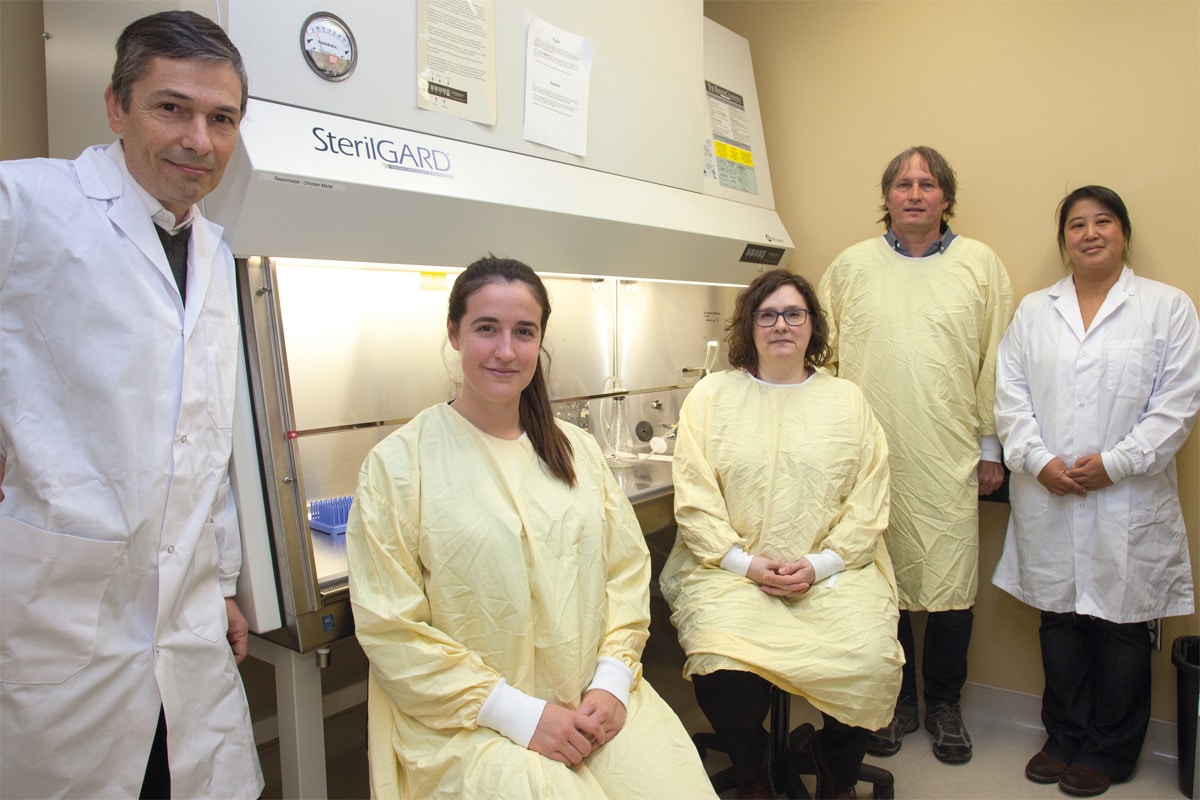

François Berthod et son équipe font repousser des nerfs sectionnés, en les guidant à l’aide d’un tube vivant.